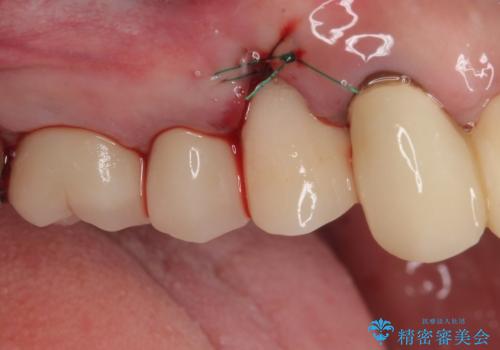

膿の出口が認められた頬側の歯槽骨は欠損が大きかったものの、インプラント埋入には十分な骨があり、無事に短期間で治療を終えることができました。